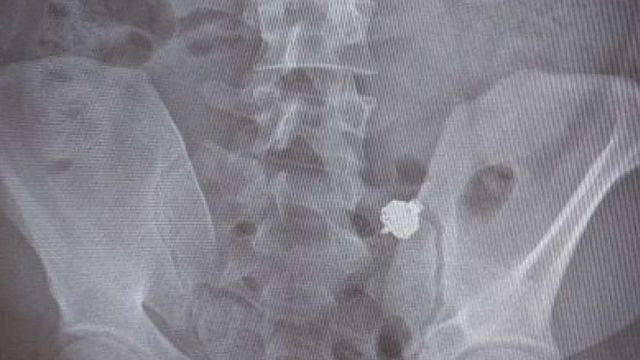

L'uomo è stato così accompagnato in ospedale e sottoposto a una radiografia, la cui lastra ha mostrato la presenza dell'auricolare nell'apparato digerente.